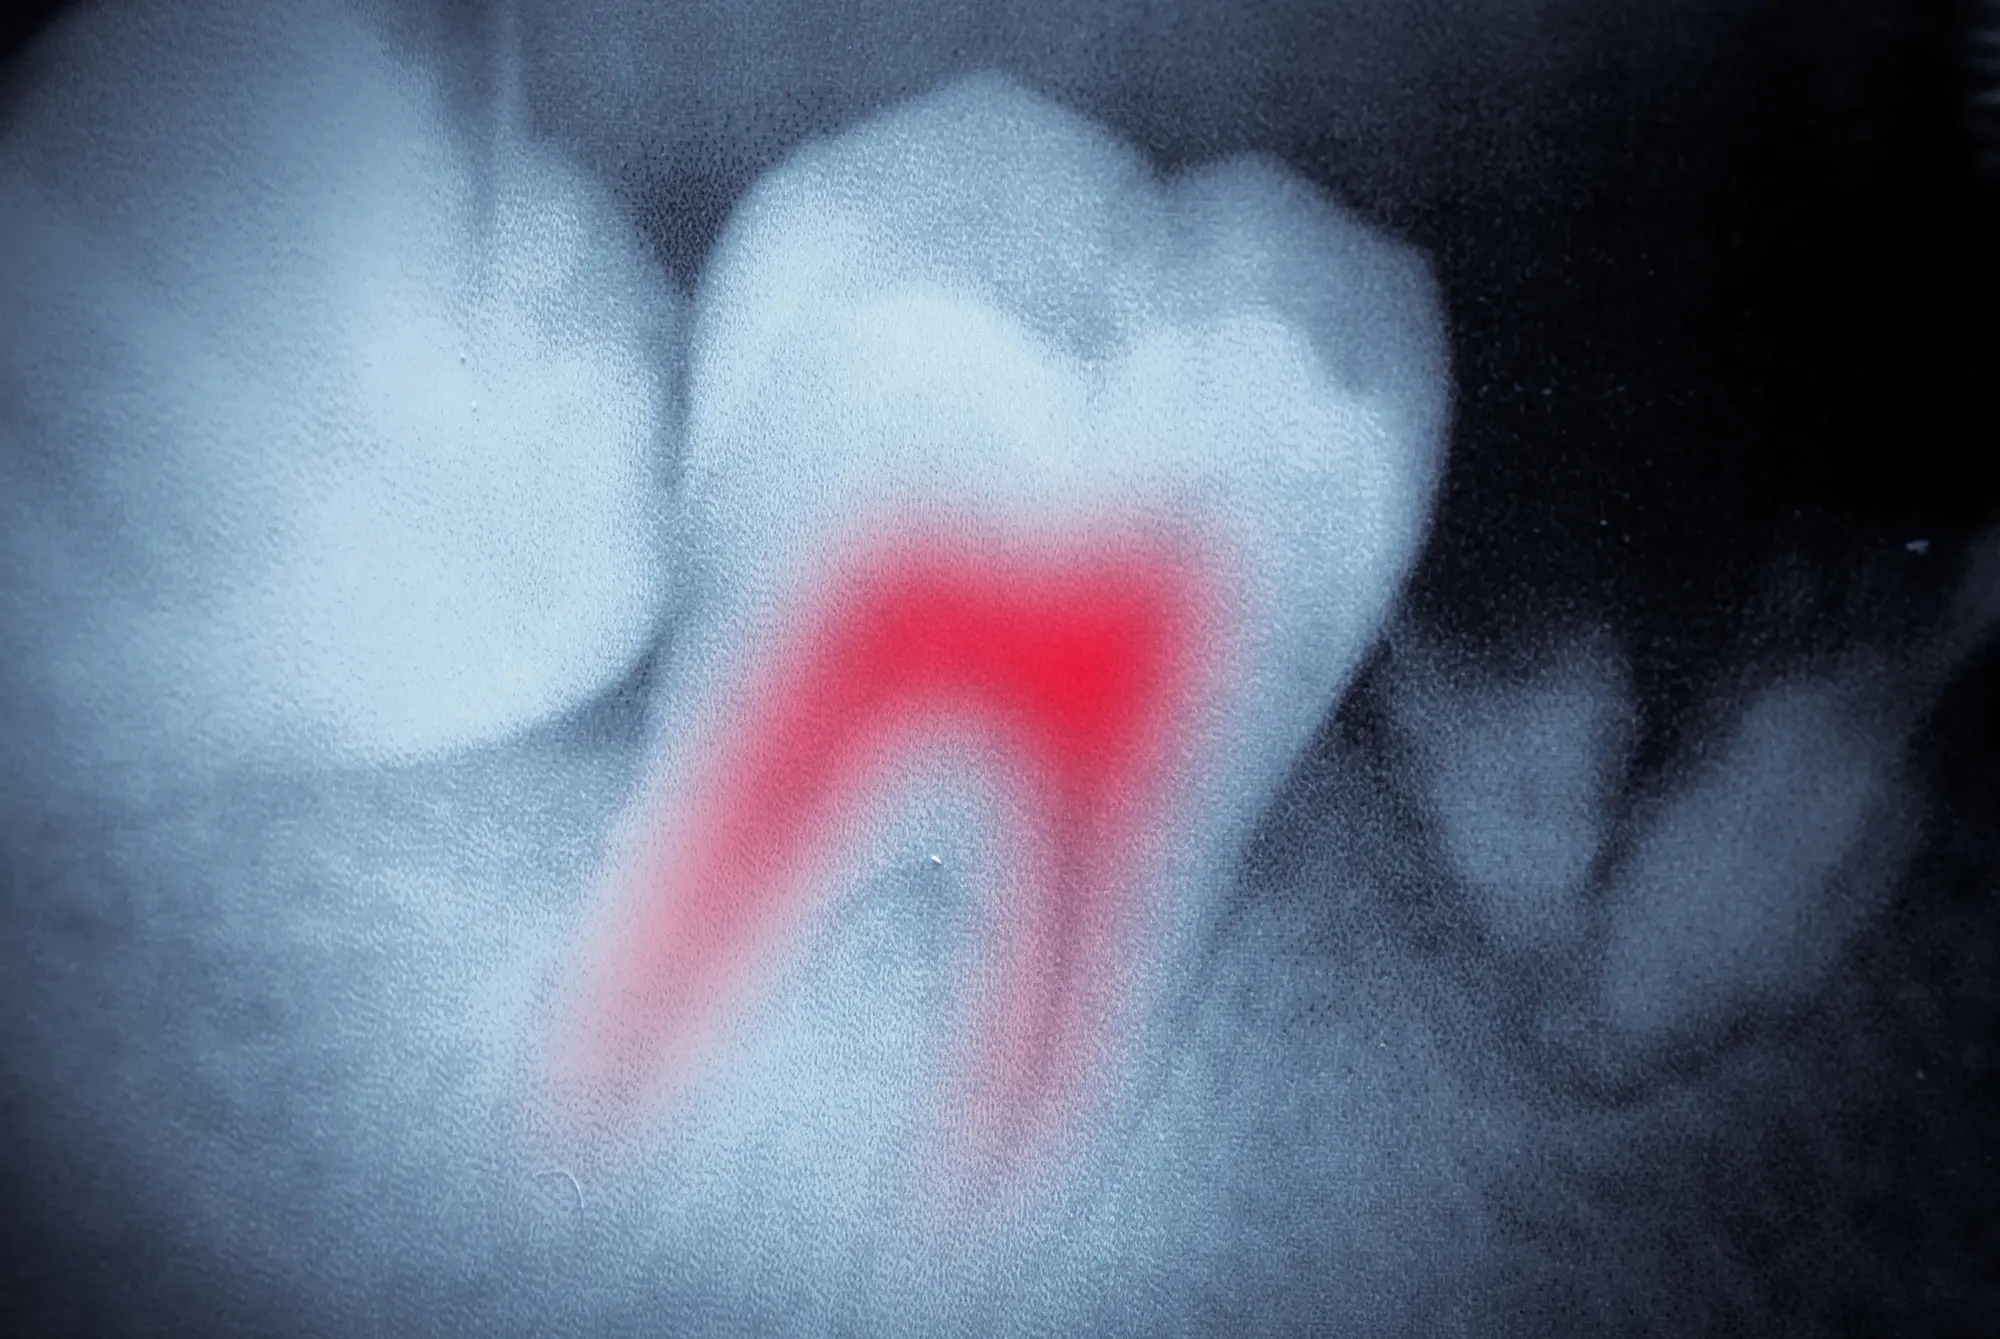

When Do You Need a Root Canal?

Root canal treatment is recommended when the pulp becomes infected due to decay, injury, cracks, or repeated dental work. You may notice symptoms like:

- Persistent tooth pain or sensitivity to hot and cold

- Swelling or tenderness in the gums near the tooth

- Visible damage, cracks, or deep decay

- Discomfort when chewing or biting